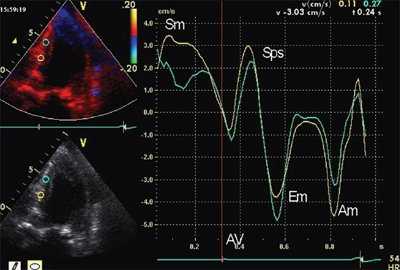

На рис. 3-5 приведены различные варианты ПСУ у больных с постинфарктным кардиосклерозом.

![Тканевая допплерография в норме. У больного с постинфарктным кардиосклерозом регистрируется высокоамплитудный пик постсистолической скорости (Sps)]()

![Тканевая допплерография при постинфарктном кардиосклерозе. У больного с постинфарктным кардиосклерозом регистрируется высокоамплитудный пик постсистолической скорости (Sps)]()

б) При постинфарктном кардиосклерозе. У больного с регистрируется высокоамплитудный пик постсистолической скорости (Sps).

- Амплитуда постсистолического пика скорости, регистрируемого в фазу изоволюмического расслабления (Sps). Вычислялось отношение скоростей Sps/Sm.

- Форма кривой движения миокарда в течение сердечного цикла. Формы кривых движения миокарда в зависимости от наличия ПСУ подразделялись на 3 типа: "норма", "ступень" и "седло".